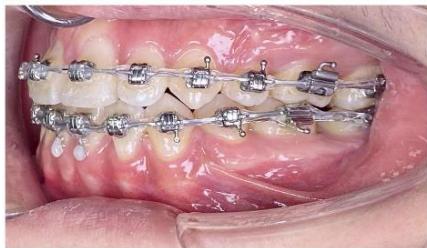

Figure 6: Canine retraction on a $0.019 \times 0.025$ -inch stainless steel archwire using sliding mechanics

During the canine retraction phase, the patient wore intermaxillary elastics (3/16-inch, 3.5 oz) from the maxillary first molars to the mandibular first and second premolars to stabilize posterior occlusal interdigitation, as canine retraction using sliding mechanics tends to generate rotational moments and increases the risk of posterior occlusal disclusion [6,7].

From the rigid archwire stage onward, an ART torque spring was placed in the mandibular four-incisor region and maintained continuously throughout the canine retraction phase. The ART appliance functioned as an auxiliary torque spring, generating active positive torque to direct the incisor roots into cancellous bone and counteract the negative torque moments produced during space closure with force application below the center of resistance [6,9]. Studies on periodontal tissue response have demonstrated that light and continuous torque forces facilitate safe alveolar bone remodeling, particularly in regions where the incisor roots are positioned close to the labial cortical plate [22,23].